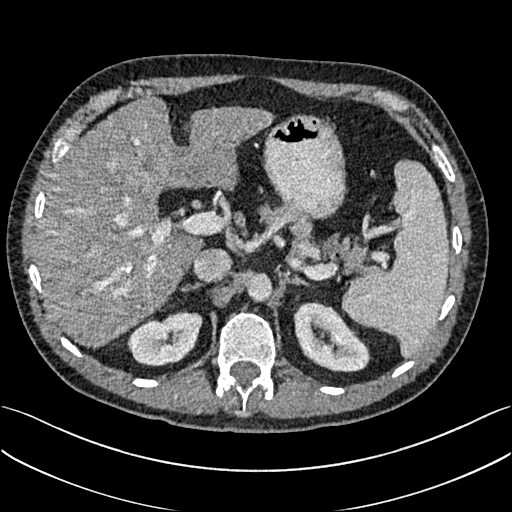

To show the denoising effect of the selected networks, we took two representative slices as shown in Figs. 5 and 7. And Figs. 6 and 8 are the zoomed regions-of-interest (ROIs) marked by the red rectangles in Figs. 5 and 7. All the networks demonstrated certain denoising capabilities. However, CNN-MSE blurred the images and introduced waxy artifacts as expected, which are easily observed in the zoomed ROIs in Figs. 6e and 8e. WGAN-MSE was able to improve the result of CNN-MSE by avoiding over-smooth but minor streak artifacts can still be observed especially compared to CNN-VGG and WGAN-VGG. Meanwhile, using WGAN or GAN alone generated stronger noise (Figs. 6g and 8g) than the other networks enhanced a few white structures in the WGAN/GAN generated images, which are originated from the low dose streak artifact in LDCT images, while on the contrary the CNN-VGG and WGAN-VGG images are visually more similar to the NDCT images. This is because the VGG loss used in CNN-VGG and WGAN-VGG is computed in a feature space that is trained previously on a very large natural image dataset [48]. By using VGG loss, we transferred the knowledge of human perception that is embedded in VGG network to CT image quality evaluation. The performance of using WGAN or GAN alone is not acceptable because it only maps the data distribution from LDCT to NDCT but does not guarantee the image content correspondence. As for the lesion detection in these two slices, all the networks enhance the lesion visibility compared to the original noisy low dose FBP images as noise is reduced by the different approaches.

As for iterative reconstruction technique, the reconstruction results depend greatly on the choices of the regularization parameters. The implemented dictionary learning reconstruction (DictRecon) result gave the most aggressive noise reduction effect compared to the network outputs as a result of strong regularization. However, it over-smoothed some fine structures. For example, in Fig. 8, the vessel pointed by the green arrow was smeared out while it is easily identifiable in NDCT as well as WGAN-VGG images. Yet, as an iterative reconstruction method, DictRecon has its advantage over post-processing method. As pointed by the red arrow in Fig 8, there is a bright spot which can be seen in DictRecon and NDCT images, but is not observable in LDCT and network processed images. Since the WGAN-VGG image is generated from LDCT image, in which this bright spot is not easily observed, it is reasonable that we do not see the bright spot in the images processed by neural networks. In other words, we do not want the network to generate structure that does not exist in the original images. In short, the proposed WGAN-VGG network is a post-processing method and information that is lost during the FBP reconstruction cannot easily be recovered, which is one limitation for all the post-processing methods. On the other hand, as an iterative reconstruction method, DictRecon algorithm generates images from raw data, which has more information than the post-processing methods.